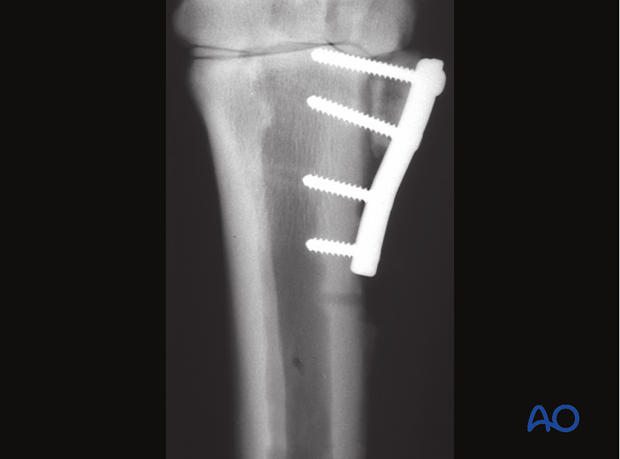

The remaining proximal stump may dislocate, which can result in significant lameness and, eventually, degenerative joint disease.

To avoid dislocation of the proximal stump, the fixation of the proximal remaining splint bone to the third metacarpal/-tarsal bone with a plate is necessary.